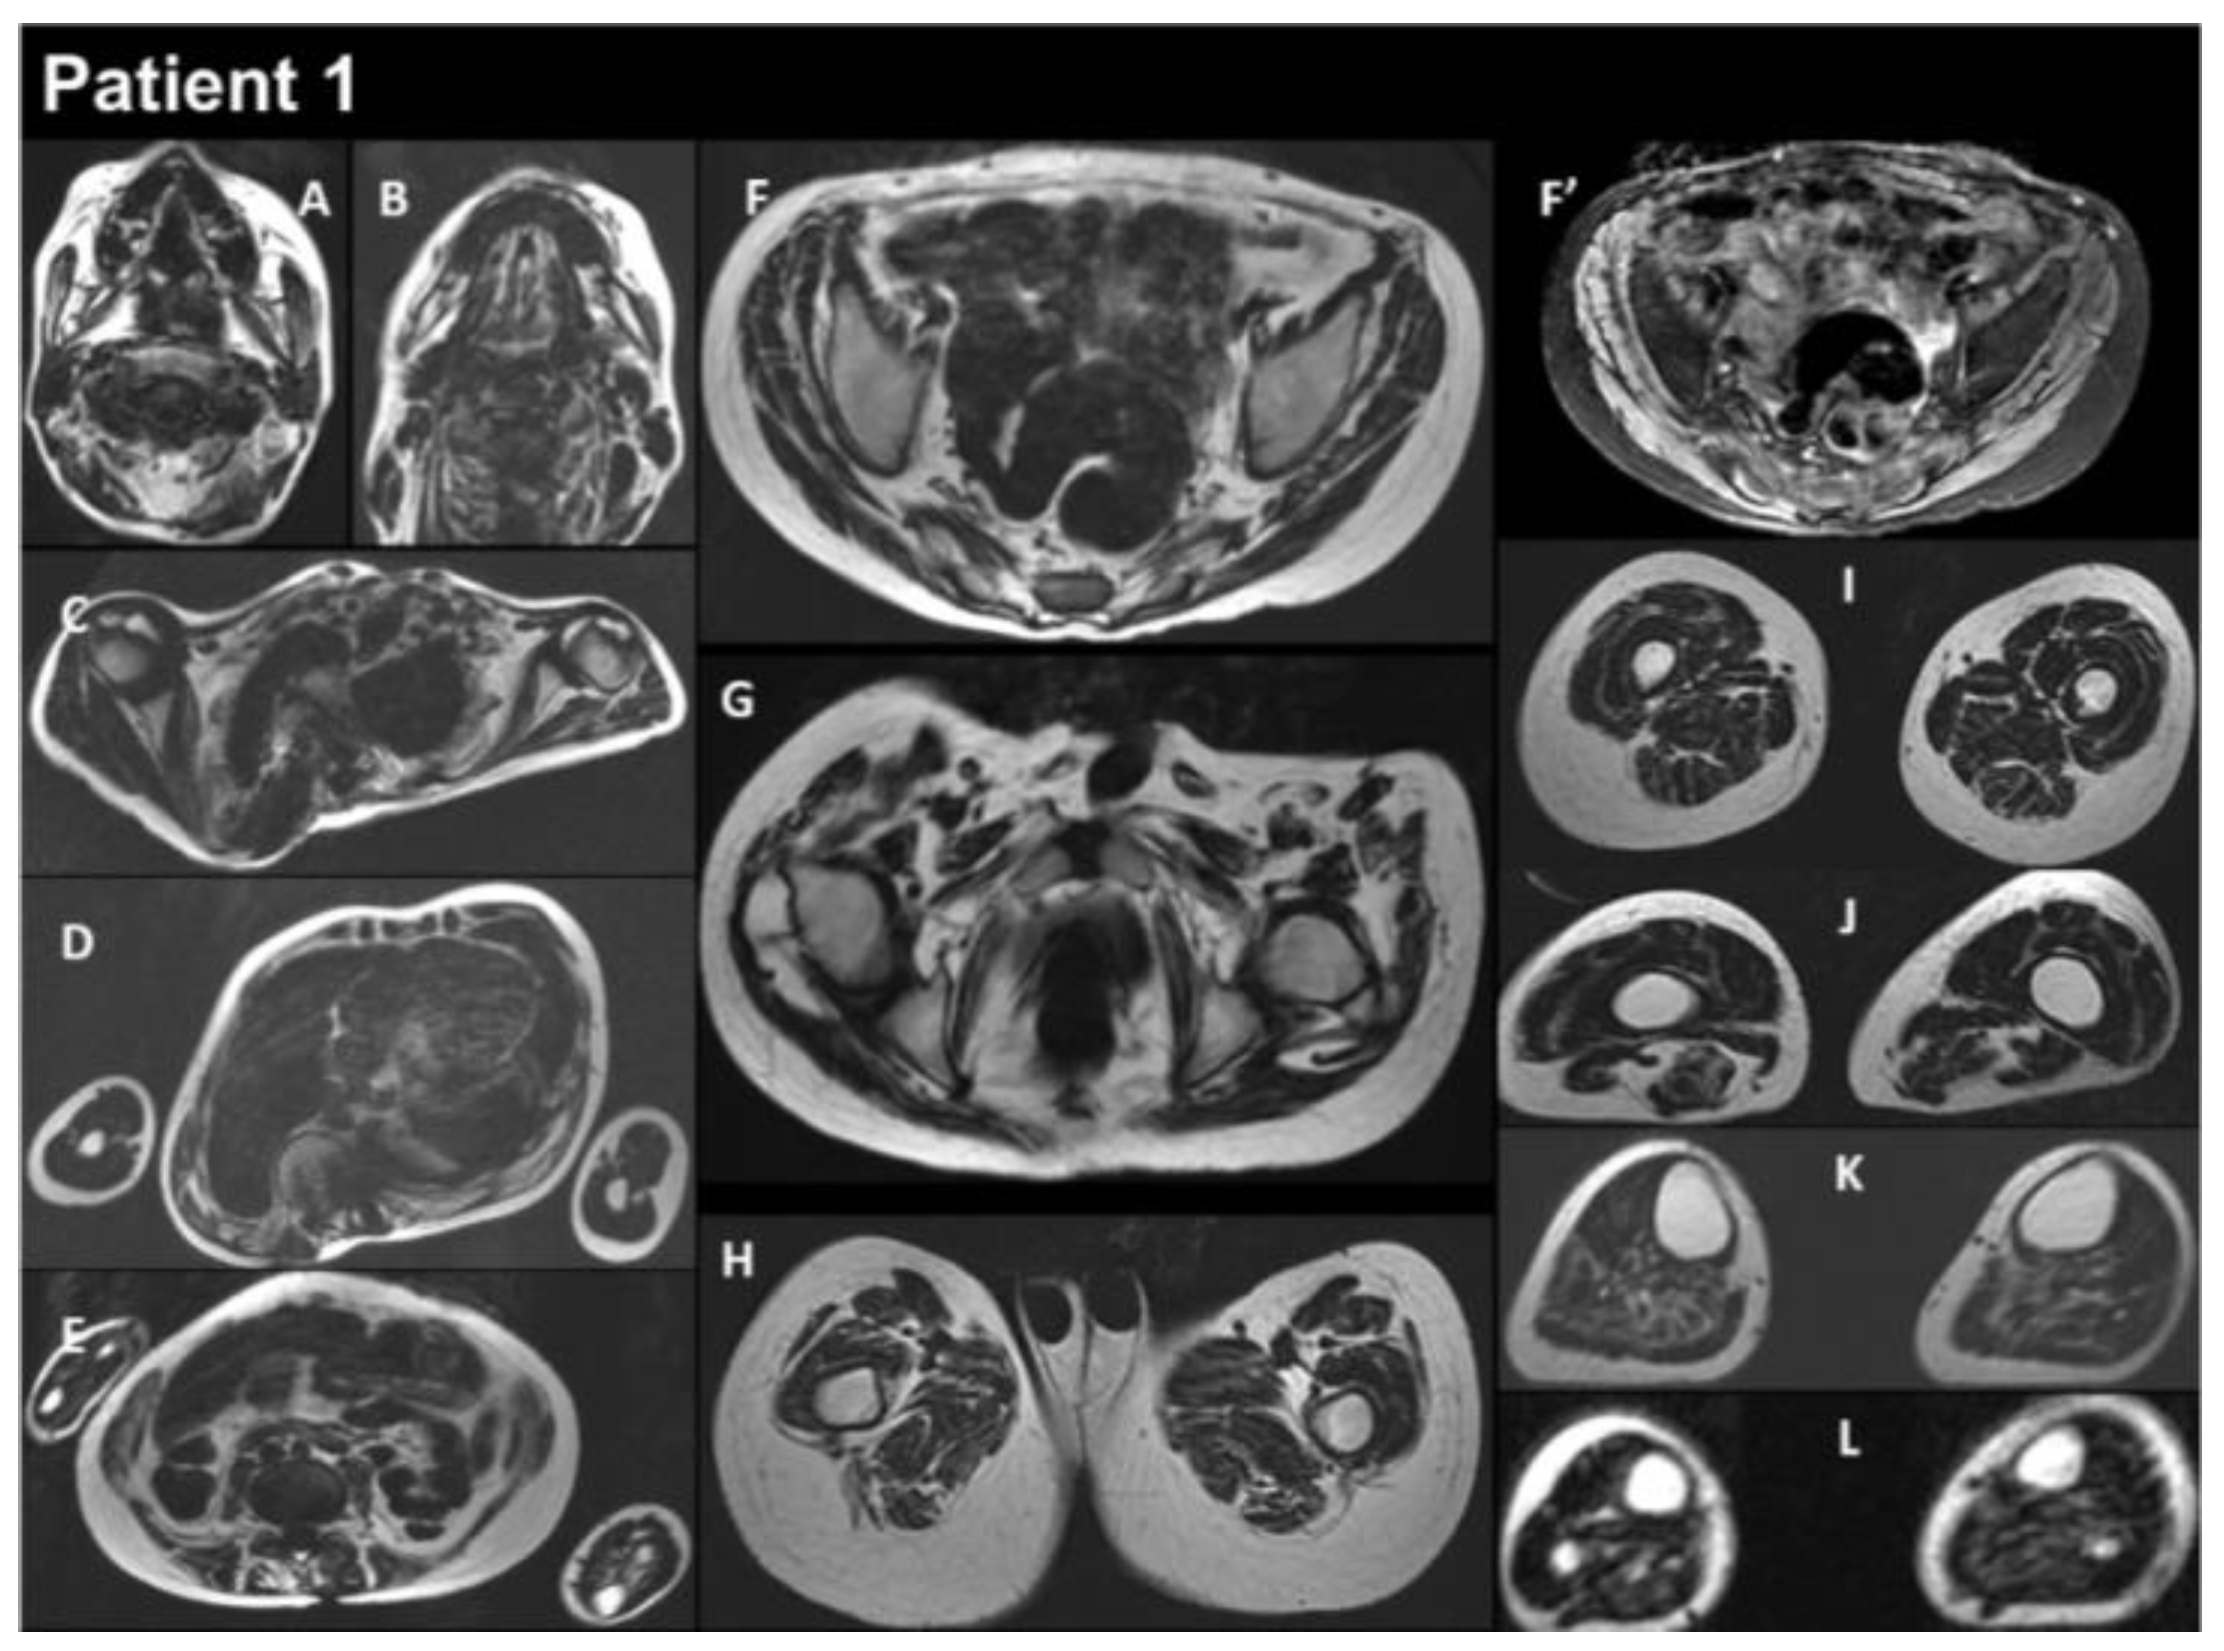

| THIS STUDY | P1 | M | heteroz., de novo | RCM + myopathy | Birth | 13 y | Global | Yes | Yes | Myopathic | Normal | RCM | Restrictive respiratory syndrome | Alive at 17 y | Yes |

| P2 | M | heteroz. | HCM + myopathy | 2 y | 39 y | Global | - | Yes | - | Increased | HCM | Restrictive respiratory syndrome | Alive at 43 y | Yes | |